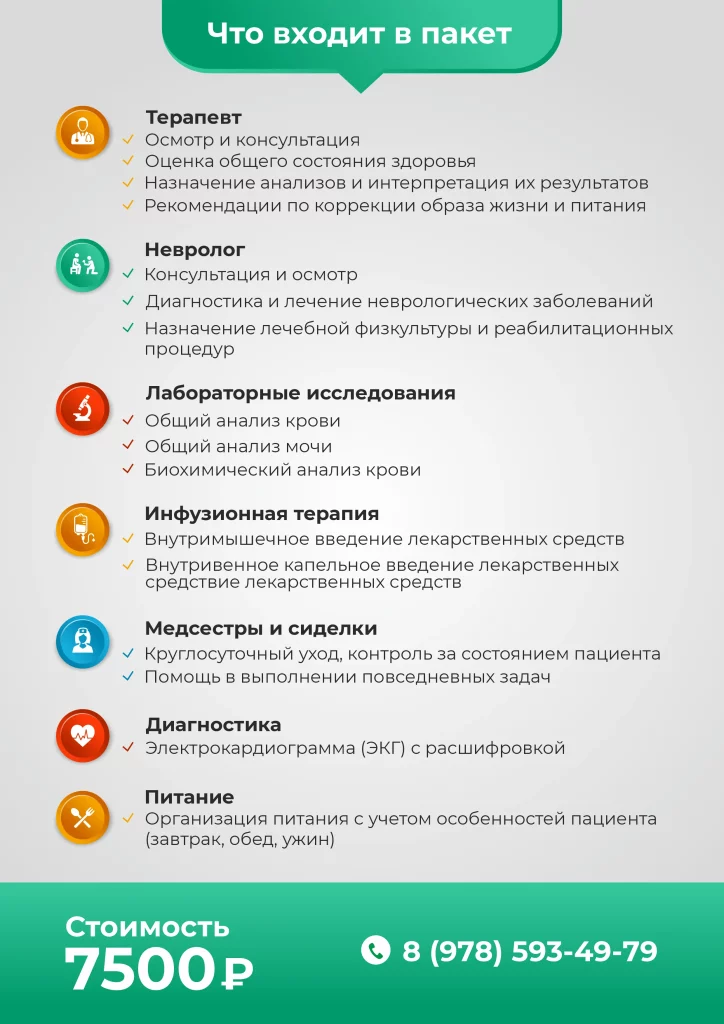

Этот пакет представляет собой наиболее комплексную программу восстановления, включающую полное медицинское сопровождение, расширенные анализы и физиотерапевтические процедуры.

Количество мест ограничено, воспользуйтесь возможностью пройти курс по сниженной цене.

Этот пакет идеально подходит для пациентов с хроническими заболеваниями, которые нуждаются в постоянном мониторинге и поддержке.

Программа включает дополнительные процедуры и регулярные осмотры врачей для поддержания стабильного состояния здоровья.

Этот пакет предназначен для тех, кто нуждается в регулярном мониторинге состояния здоровья.

Он идеален для профилактики и ранней диагностики, предоставляя основные медицинские услуги для поддержания стабильного состояния.

Программа VIP-реабилитации — это максимальный комфорт, индивидуальный подход и исключительный уровень медицинского обслуживания. Каждая деталь программы создается с учетом ваших личных потребностей, а премиальные услуги обеспечат вам наиболее эффективное и комфортное восстановление. Все включено, включая уникальные VIP-услуги, которые помогут вам быстрее вернуться к полноценной жизни.

В пакет входят все услуги из пакета «Комплексная реабилитация»

Консультации специалистов: терапевт, невролог, кардиолог, реабилитолог, психолог.

Лечебная физкультура, массаж, механотерапия, парафинотерапия.

Лабораторные исследования: общий анализ крови, общий анализ мочи, биохимический анализ крови, клинический анализ с лейкоцитарной формулой.

Круглосуточный уход и помощь сиделок.